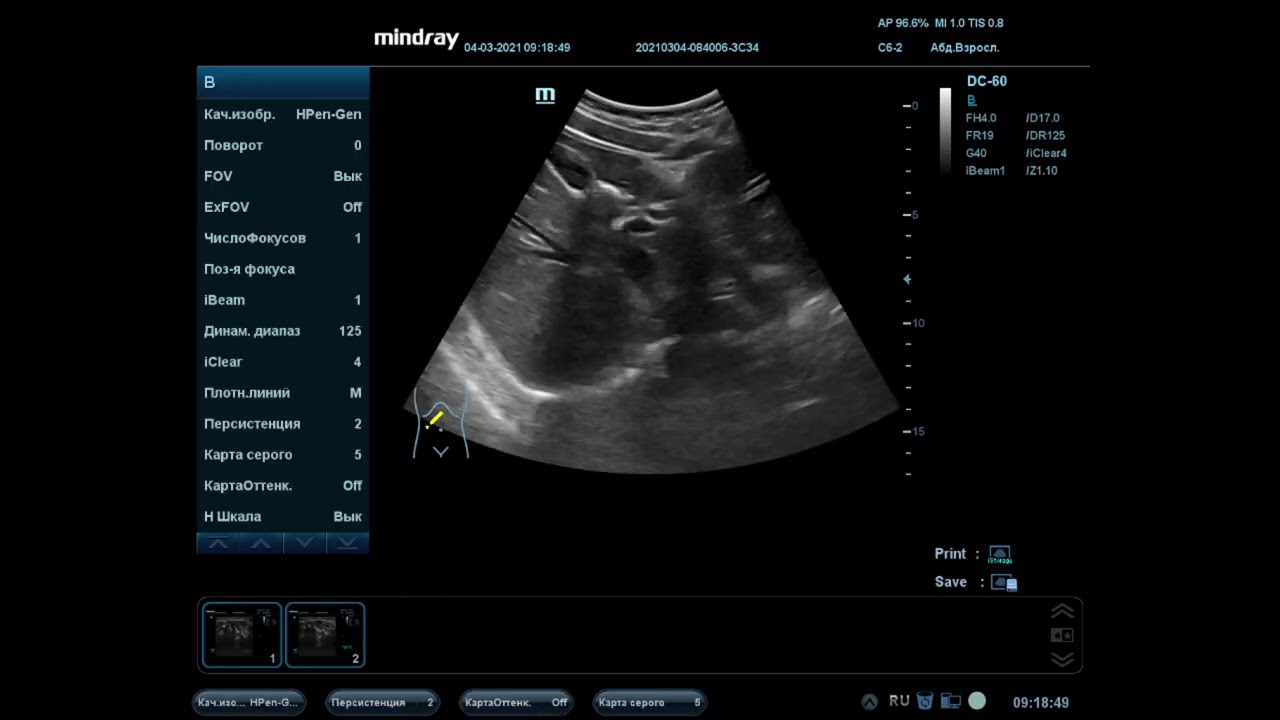

Изранов лекции печень

Изранов лекции печень 112 фотографий